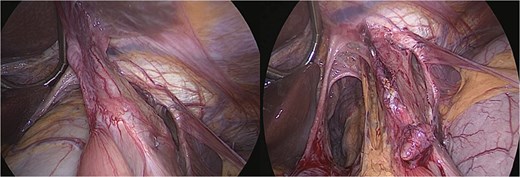

An urgent laparoscopic exploration was performed, revealing a large hiatal defect with exposure of the posterior mediastinum and aorta. The proximal portion of the gastric remnant remained within the abdominal cavity, while the distal remnant and duodenum had herniated into the thoracic cavity and exhibited rotation. The remnant stomach was found to be significantly distended and edematous, containing ~3 l of coffee-ground fluid. Additionally, the entire gastric pouch and gastrojejunal anastomosis were discovered herniated within the chest (Fig. 2).

Intraoperative view—large hiatal defect before and after reduction herniated viscera.

Surgical management involved reducing all herniated abdominal organs from the thoracic cavity. To address the distention of the gastric remnant, a gastrotomy was performed to evacuate the accumulated fluid (Fig. 3). This was followed by a primary hiatal repair using an anterior approach, and resection of the remnant stomach up to the level of the duodenum (Fig. 4).